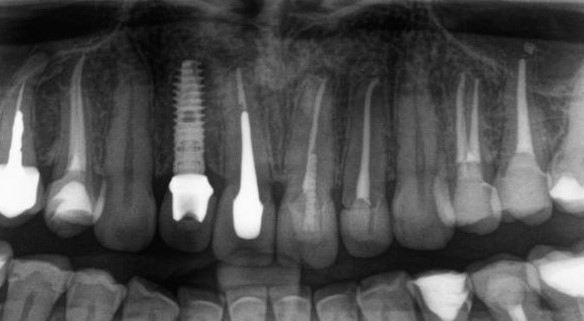

По мнению абсолютного большинства, под периимплантитом подразумевается воспалительный процесс, сопровождающийся выраженными органическими (видимыми) изменениями окружающих имплантат тканей. Чаще всего мы говорим про периимплантит, когда видим резорбцию костной ткани вокруг имплантата:

С этого момента возникает довольно серьёзная методологическая проблема: далеко не всегда деструкция костной ткани сопровождается хоть какой-то воспалительной симптоматикой. Как, например, здесь:

Снимок сделан примерно через 8 лет после имплантации. 65-летняя пациентка никакой воспалительной симптоматики не отмечает, говорит, что никогда ничего не болело и не воспалялось. Можно ли считать такой случай периимплантитом?

С одной стороны, убыль костной ткани налицо, но её причиной может быть, в том числе, обычная атрофия (всё же, возраст и состояние организма…). С другой, отсутствие каких-либо признаков воспалительного процесса в анемнезе и при объективном осмотре. Назвать этот случай периимплантитом нельзя, убыль костной ткани в этом случае вызван физиологической атрофией, связанной, в т. ч., с вышеозначенными причинами.